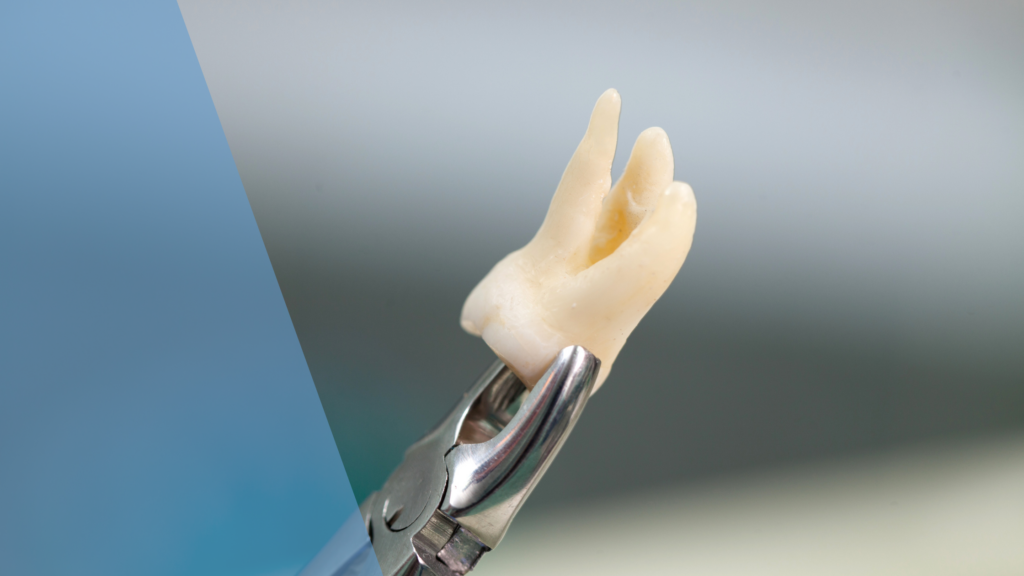

The Complete Guide to Wisdom Teeth Extractions: Before, During, and After

Planning wisdom teeth extractions? This comprehensive guide from Dental Arts Toronto covers pre-operative preparation, the step-by-step procedure, anesthesia options, and detailed recovery timeline to help you know exactly what to expect.